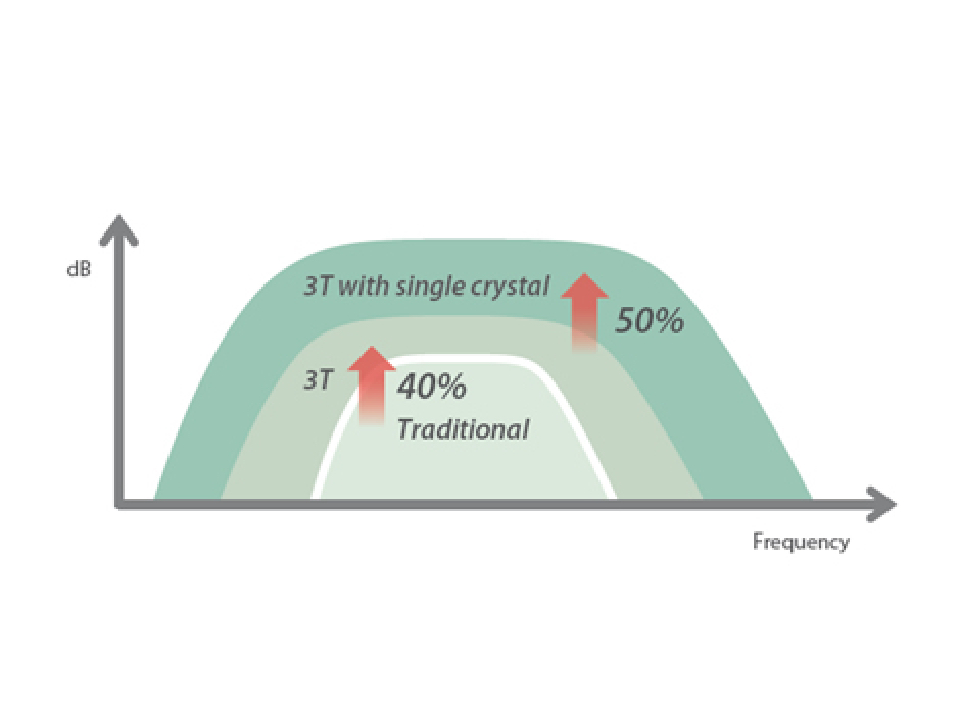

X-Insight

X-Insight is an insightful solution to envision more.

MindrayŌĆÖs brand-new solution is an excellent transforming of continuous customer insights into clinical needs, combined with evolving cutting-edge ultrasound technologies.

Based on deep insights into customer needs, the DC-70 with X-Insight is designed to deliver high efficiency with precision imaging, which is empowered by eXpress Clarity and eXceptional Intelligence, and benefits from eXceeding Experience.